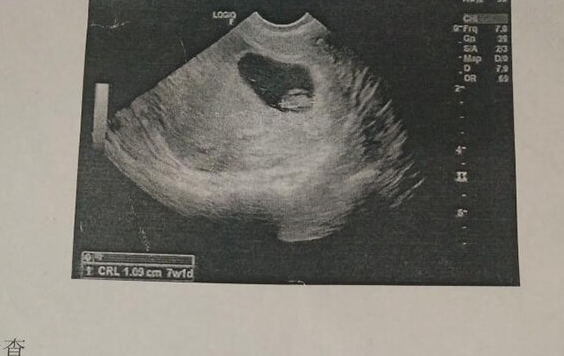

孕囊呈椭圆形或者圆形生女孩,孕囊呈长条形生男孩。这种说法是民间经验所得,并没有科学依据,其结果也并不准确,孕囊的形状并不能判断男孩女孩。胚胎在12mm以前进行B超检查,基本都是三维的球体或椭圆体,偶尔也会出现长条形。而在B超的观察下见到的孕囊也只是三维结构的一个切面,孕囊位置不同,B超下观察的孕囊形状也是有变化的。孕囊形状是判断胚胎发育的一个重要依据,通常女性在停经5-6周以后通过超声检查可见,形状一般是圆形或椭圆形;若孕囊呈不规则形状,可能是孕囊发育不良的一种表现。因此,孕囊的形状不能判断宝宝的性别。

孕囊圆形为女孩,长条形为男孩的说法并没有科学依据,孕囊的形状主要是判断胚胎的发育情况,需要结合胎芽、胎心的情况,并不能判断宝宝的性别。在B超检查中,孕囊的形状呈不规则性的需要引起注意,谨防出现发育不良的情况。怀孕的夫妻不必过于执着宝宝的性别,宝宝的健康发育才是最重要的。